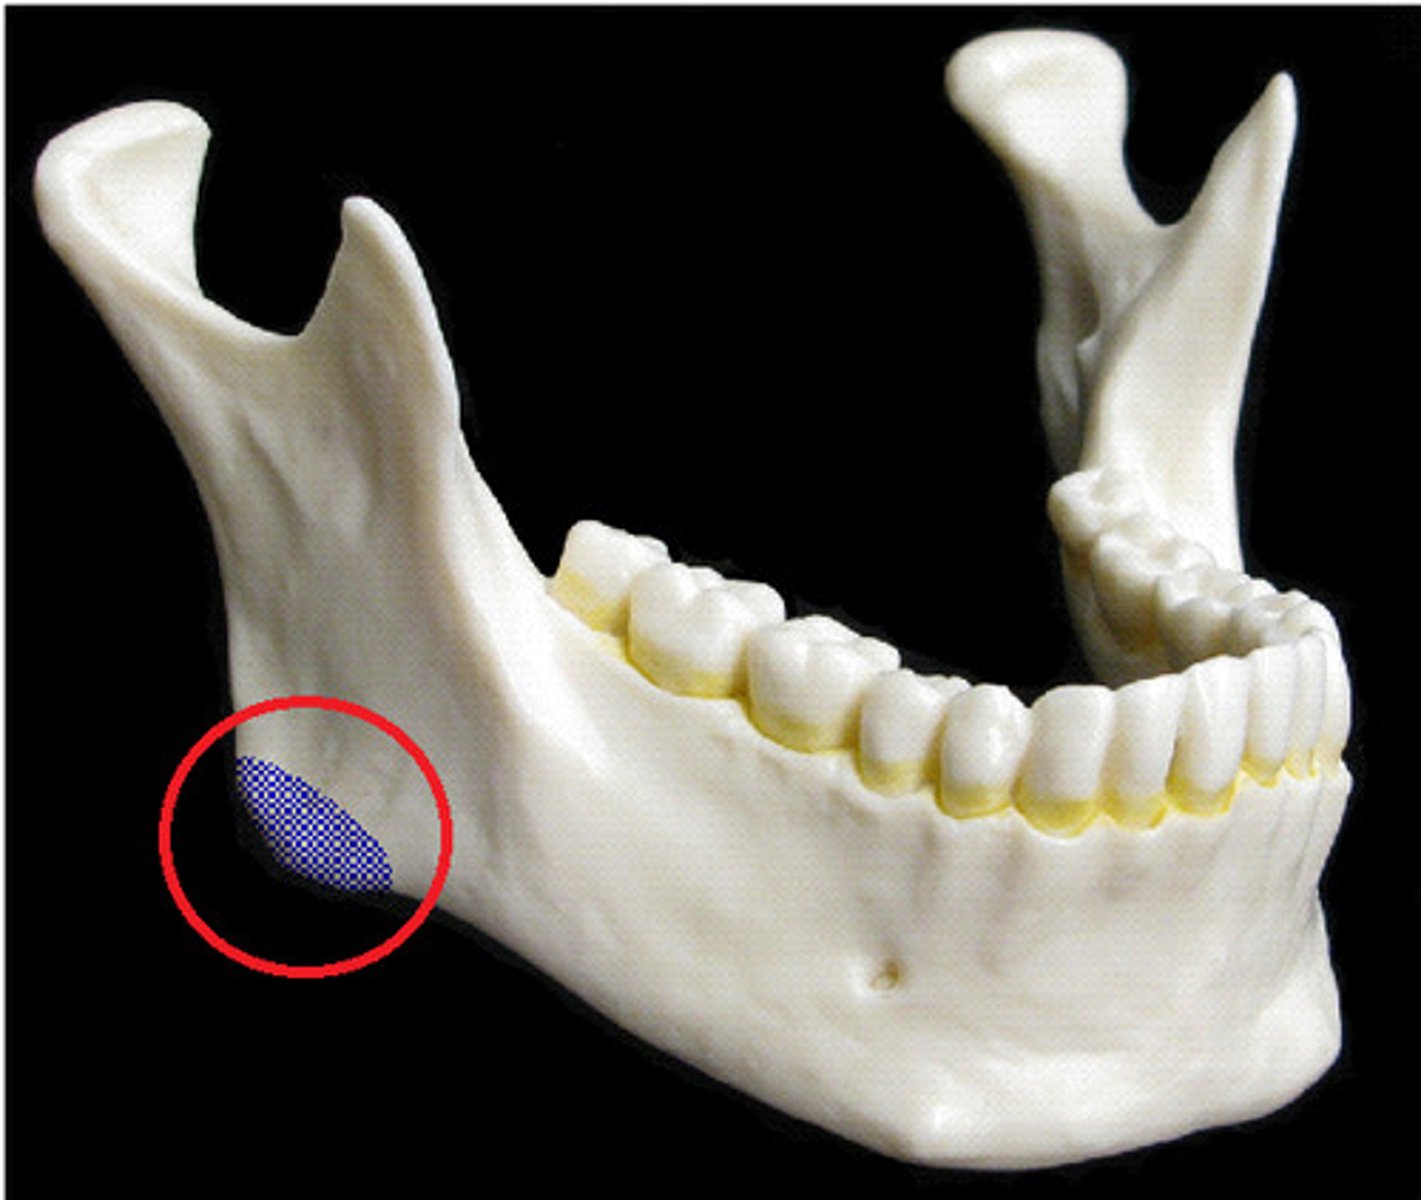

Mandible Body (Mandible)

horizontal portion of the mandible

mandible angle

where the body and ramus of the mandible meet, attachment of the masseter laterally, and the pterygoideus internus (medial pterygoid muscle) medially; the stylomandibular ligament is attached to the angle between these muscles.

mandible ramus

vertical extension of the body on either side

coronoid process of mandible

insertion of temporalis

head of mandible

round portion at the top of the condylar process; articulates with temporal mandibular fossa

alveolar part of mandible

houses the teeth in dental alveoli (sacs)